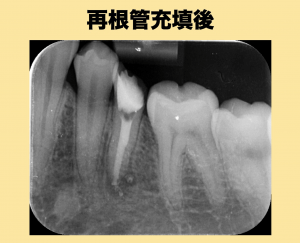

レントゲンを撮影してみると根先部に限局した透過像が認められます、そのため再感染根管治療を行いました。

その後、ビタペックスにて仮の根管充填で経過観察を行っていましたが治癒しないために外科的歯内療法を行うこととなりました。

今回は術後の経過も良好でフィステルも消失し根尖部の透過像も綺麗に消失しているので一安心です。